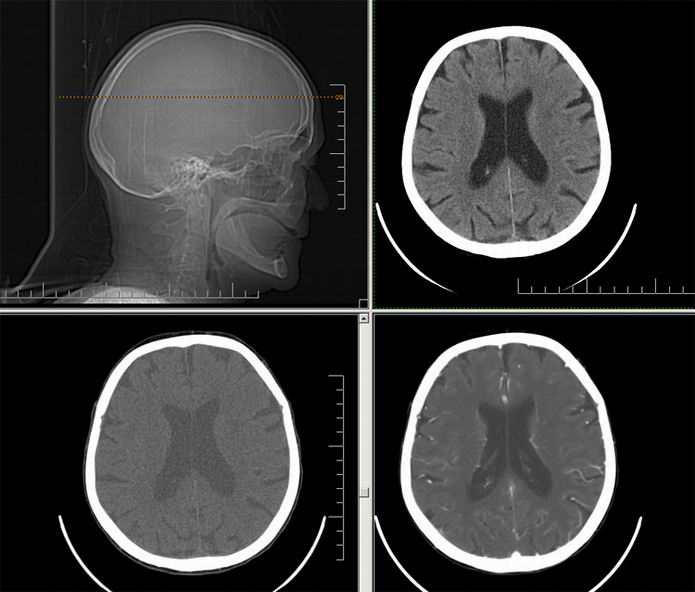

Est ce que qqun a des coupes axiales de crâne pour m'aider à réviser mon anatomie. Merci

Pour compléter tes révisions, Poupette vient de nous faire parvenir ces planches bien utiles: Planches de coupes axiales cérébrales, dans la rubrique COURS / ANATOMIE